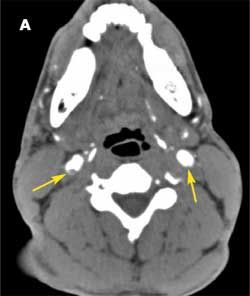

The patient was admitted with a diagnosis of stroke. A CT scan of the brain revealed no bleeding or infarction. A CT angiogram showed bilateral internal carotid dissection, on the right more than the left (A). A heparin drip and aspirin were started. MRI done 24 hours later showed acute infarction in the right basal ganglia and to a smaller degree in the right temporal lobe (B); petechial hemorrhages were noted in the acute infarction. At this point, the heparin drip and aspirin were discontinued. The patient could not be anticoagulated because of the hemorrhagic conversion.